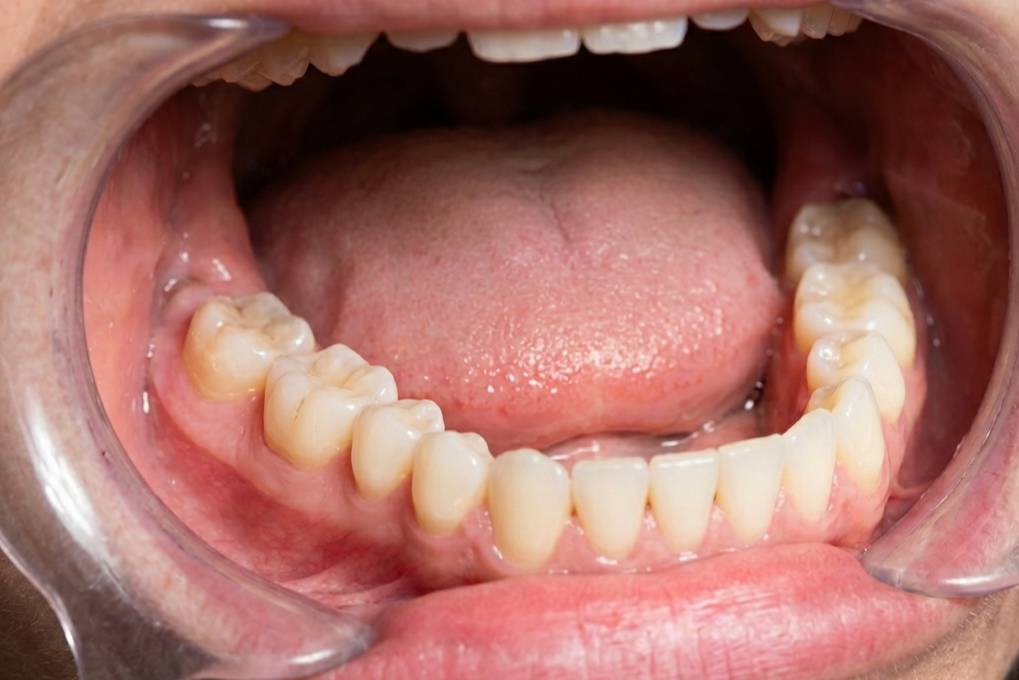

When a wisdom tooth doesn’t have enough room to emerge, it becomes “impacted.” This means it remains stuck in the jawbone or grows in sideways, pressing against the roots of neighboring teeth. This isn’t just a minor discomfort; it can lead to cysts, gum disease, and even damage to the jawbone itself. In the modern world, this is one of the most common reasons for outpatient surgery. Because our mouths have evolved to be smaller, these “trapped” teeth have become a significant health hurdle that our ancestors rarely had to deal with during their shorter lifespans.

Dentists generally monitor these teeth with X-rays starting in the early teens to catch potential problems before they start. If a tooth looks like it’s going to cause a “pile-up” in the dental row, extraction is usually the safest bet. This medical necessity highlights the gap between our ancient biology and our current needs. We are essentially living in a high-tech world with “hardware” that was designed for a much rougher environment. Dealing with impacted wisdom teeth is simply part of the price we pay for having the refined, smaller faces that characterize the modern human look today.